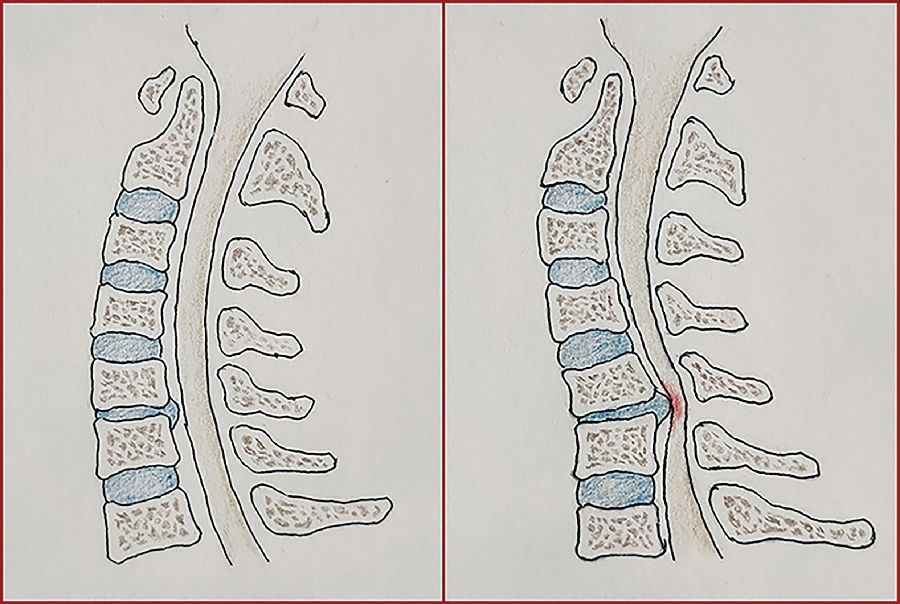

既往有学者利用动物模型,发现颈椎后凸可致神经元凋亡和轴索脱髓鞘改变,这可能是由于颈椎后凸对后方脊髓持续性机械压迫和并减少脊髓血供引起的。我们的研究也发现存在明显退变性颈椎后凸的患者中(大于10°),超过80%的情况下,后凸节段往往也是颈椎磁共振上压迫最重的节段。除了颈椎间盘突出压迫或颈后纵韧带骨化压迫,退变性颈椎后凸也可通过局部形态学改变,对后方脊髓神经的机械产生压迫或牵拉;亦或是通过局部形态学改变,加重原有因间盘或颈后纵韧带骨化产生的压迫。这一发现也再次印证了退变性颈椎后凸导致神经功能损害的潜在病理机制(图8)。因此颈椎局部后凸在术前规划中也应该考虑,并在手术减压同时进行纠正,消除其对神经功能的潜在影响。但是多大后凸角度容易导致神经功能受损呢?

图8.颈椎节段性后凸可能加重脊髓压迫程度示意图。左图显示颈椎间盘轻中度突出,曲度正常时未对脊髓造成明显压迫;右图显示相似程度的颈椎间盘突出,在合并退变性颈椎后凸的情况下,可能会对脊髓造成压迫